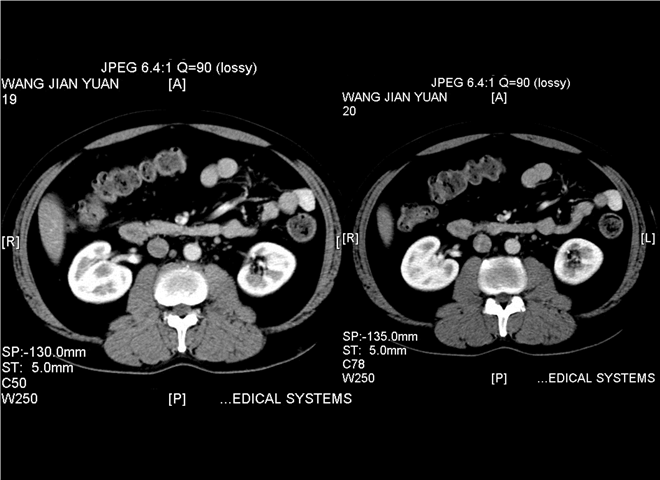

13_CT增强扫描